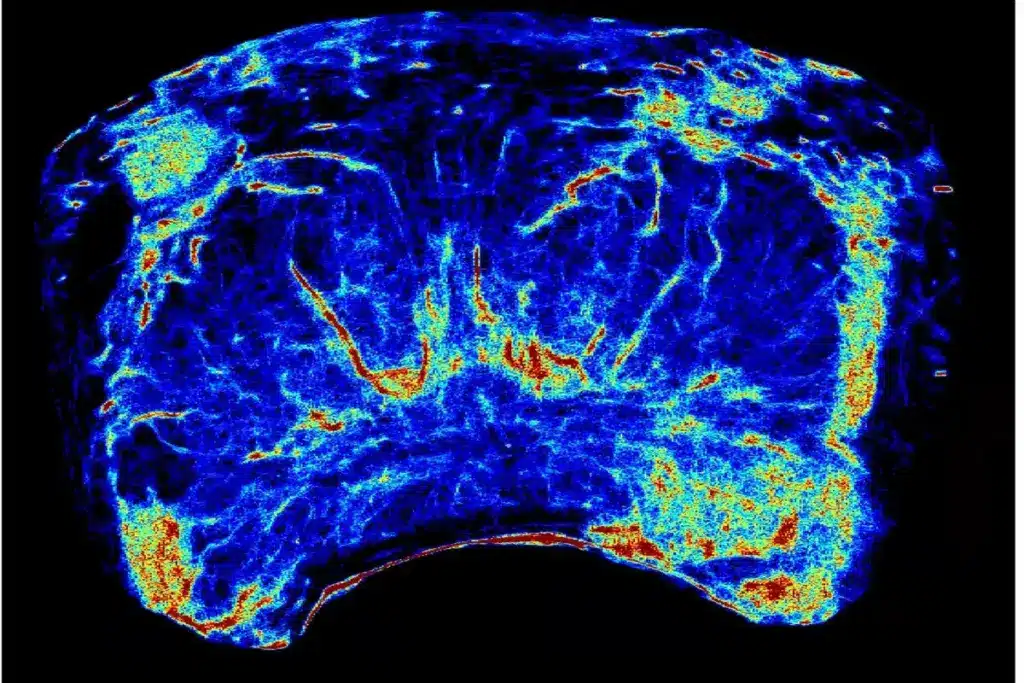

There are various MRI methods for prostate checks, like multiparametric MRI (mpMRI). Multiparametric MRI uses several sequences for a full prostate check. This includes T2-weighted, diffusion-weighted, and dynamic contrast-enhanced imaging.

mpMRI has made finding and understanding prostate cancer better. It spots important cancers and misses small ones.